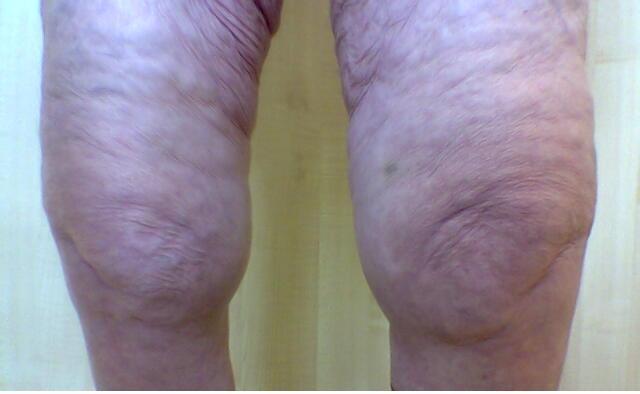

2. Deformidad en varo

1. 50% TOT gonartrosis

2. Derrame articular

3. COMPLICACIONES

1. Derrame articular, herniación capsular, bloqueo articular, tendinitis, estenosis espinal, espondilolistesis